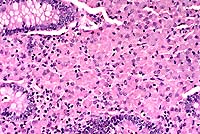

Contributor's Diagnosis and Comments: Lung: Pneumonia,

broncho- interstitial, multifocal, acute, severe, necrotizing,

with intranuclear viral inclusions.

Etiology: feline herpesvirus-1 (feline rhinotracheitis virus)

The kittens died of severe necrotizing pneumonia caused by

feline herpes- virus (FHV-1) infection. Significant microscopic

changes were confined to the lungs. Multifocally, bronchi and

bronchioles were necrotic and filled with fibrin, neutrophils

and cellular debris. There was multifocal patchy necrosis of alveoli,

with flooding of lumina with fibrin and cellular debris. In less

affected areas, alveolar septa were thickened by neutrophils,

fibrin and edema, with numerous microthrombi within alveolar capillaries.

Alveolar lumina contained small to moderate numbers of neutrophils

and fibrin. The stroma surrounding arteries and arterioles was

edematous and infiltrated by lymphocytes, macrophages and neutrophils.

The pleura was multifocally thickened by macrophages, neutrophils

and fibrin. Nuclei of remaining airway epithelial cells were occasionally

cleared, with margination of the chromatin and smudgy to discrete

eosinophilic inclusions. Indistinct, smudgy eosinophilic inclusions

were also found in scattered alveolar septal cells, surrounded

by a dark rim of marginated chromatin. Necrotizing bronchitis,

bronchiolitis and pneumonia with intranuclear eosinophilic viral

inclusion bodies are diagnostic of that agent. Transmission electron

microscopy on formalin fixed tissue was used to confirm the diagnosis;

typical 100-105 nm unenveloped icosahedral viral particles were

readily demonstrated in bronchial epithelial cell nuclei. In some

of the sections, typical type A Cowdry inclusions were difficult

to identify, due to the extensive necrosis of the bronchial/bronchiolar

epithelium.